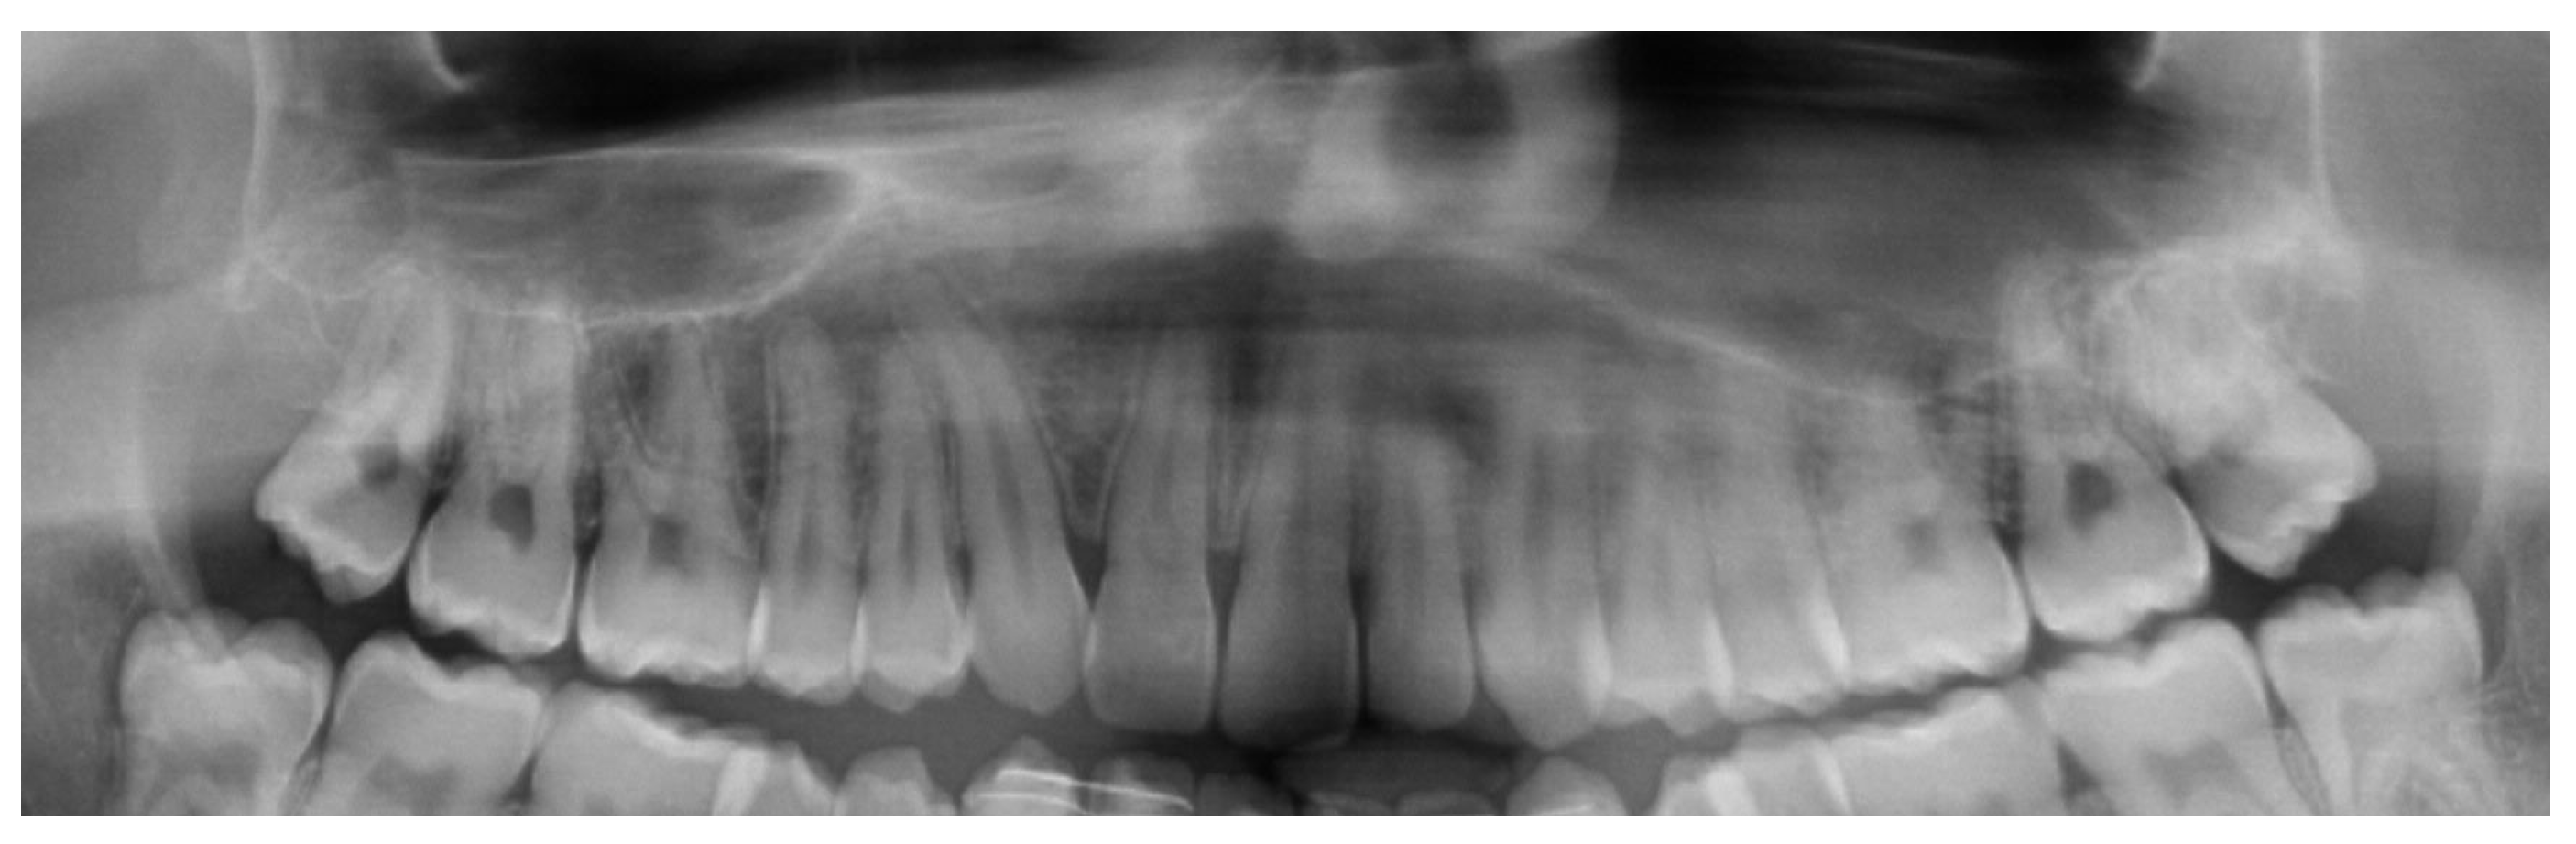

Pre-Surgical Orthodontic Treatment

- Conventional fixed appliances technique

- Clear aligner technique